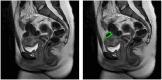

Approach: We retrospectively analyzed 44 expertly outlined UFs from 20 patients who underwent two multi-parametric MR imaging exams as part of a prospective study over an average of 16 months. We identified 44 initial features by extracting quantitative magnetic resonance imaging (MRI) features plus morphological and textural radiomics features from DCE, T2, and apparent diffusion coefficient sequences. Principal component analysis reduced dimensionality, with the smallest number of components explaining over 97.5% of the variance selected. Employing a leave-one-fibroid-out scheme, a linear discriminant analysis classifier utilized these components to output a growth risk score.